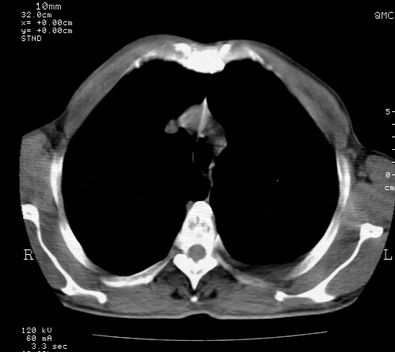

标题: CT24000:M65,胸痛,胸闷月余,既往慢支,肺气肿,肺心病 [打印本页]

标题: CT24000:M65,胸痛,胸闷月余,既往慢支,肺气肿,肺心病

左肺门肿块,相应支气管闭塞,左肺上叶、舌叶大片及散在高密度影,部分呈不张改变,两肺纹粗乱,左侧胸腔积液。考虑左侧中央型肺癌伴阻塞性改变。

左肺门见巨大软组织肿块影,直径约--,境界清,左上肺叶支气管变窄,左上肺舌叶见大片状密实影,余肺纹理增多、紊乱、纤细、部分网格状,两肺透亮度增高,纵隔内见增大多发淋巴结影,心影略左偏,左侧少量胸腔积液。

左侧中央型肺癌伴左上肺舌叶不张、纵隔淋巴结转移,左侧少量胸腔积液。